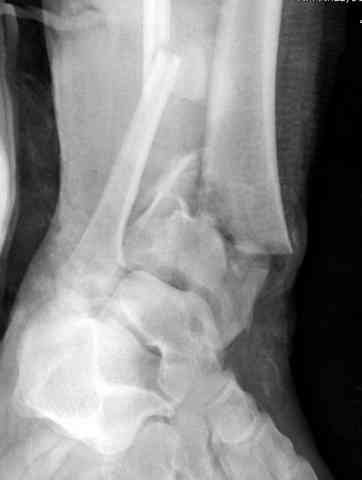

Добавлены КТ снимки. Прошу прощения за качество.

С уважением, Коваленко А.Н.

Снова приветствую вас, коллеги. К моменту вступления в обсуждение аксакалов, операция была, увы, выполнена(31.10.07.) Начали с доступа к наружной лодыжке, произвели ее фиксацию спицами, развернули кусок заднего края, наложили дистрактор, затем произвели дистракцию, фиксацию спицами дистального эпиметафиза б/бк,Рентгено-контроль. синтез наружной лодыжки 1/3пластиной. из двух коротких разрезов сформирован канал под медиальную тибиальную пластину LCP. Края ран ушиты без натяжения. Прочувствовать жесткость фиксации винтами с угловой стабильностью не удалось, поэтому дистрактор оставлен на энное время.

На представленных R-снимках не окончательный вид после остеосинтеза. Дистальная опора давила на стопу, пришлось ее сместить проксимально, в рез-те чего, она закрыла щель сустава, последние снимки не информативны.

У меня вопрос. Почему проксимальный фрагмент с медиально стороны фиксированк плате всего одним болтом.

Дистальные винты как-то чуть не все идут не в дистальные отломки, а в зону перелома. И действительно, присоединяюсь к вопросу Якова - в диафизе так и оставили 1 винт?

Честно признаться тяжело на душе после такой операции,-было всё хорошо после первоначальной дистракции, хорошая редукция отломков, после остеосинтеза пластинами появилась подвывых стопы кнаружу, от пластини LCP никакой толку-дистальные винты в зоне излома и дистальный отломок не охвачен, проксимально всего один винт, дистальные винты из м/б кости проходят сквоз сустава и упирается в таранку, стопа в эквинусном положении.Если даже всё обойдется, этот сустав нормально не будет работат.